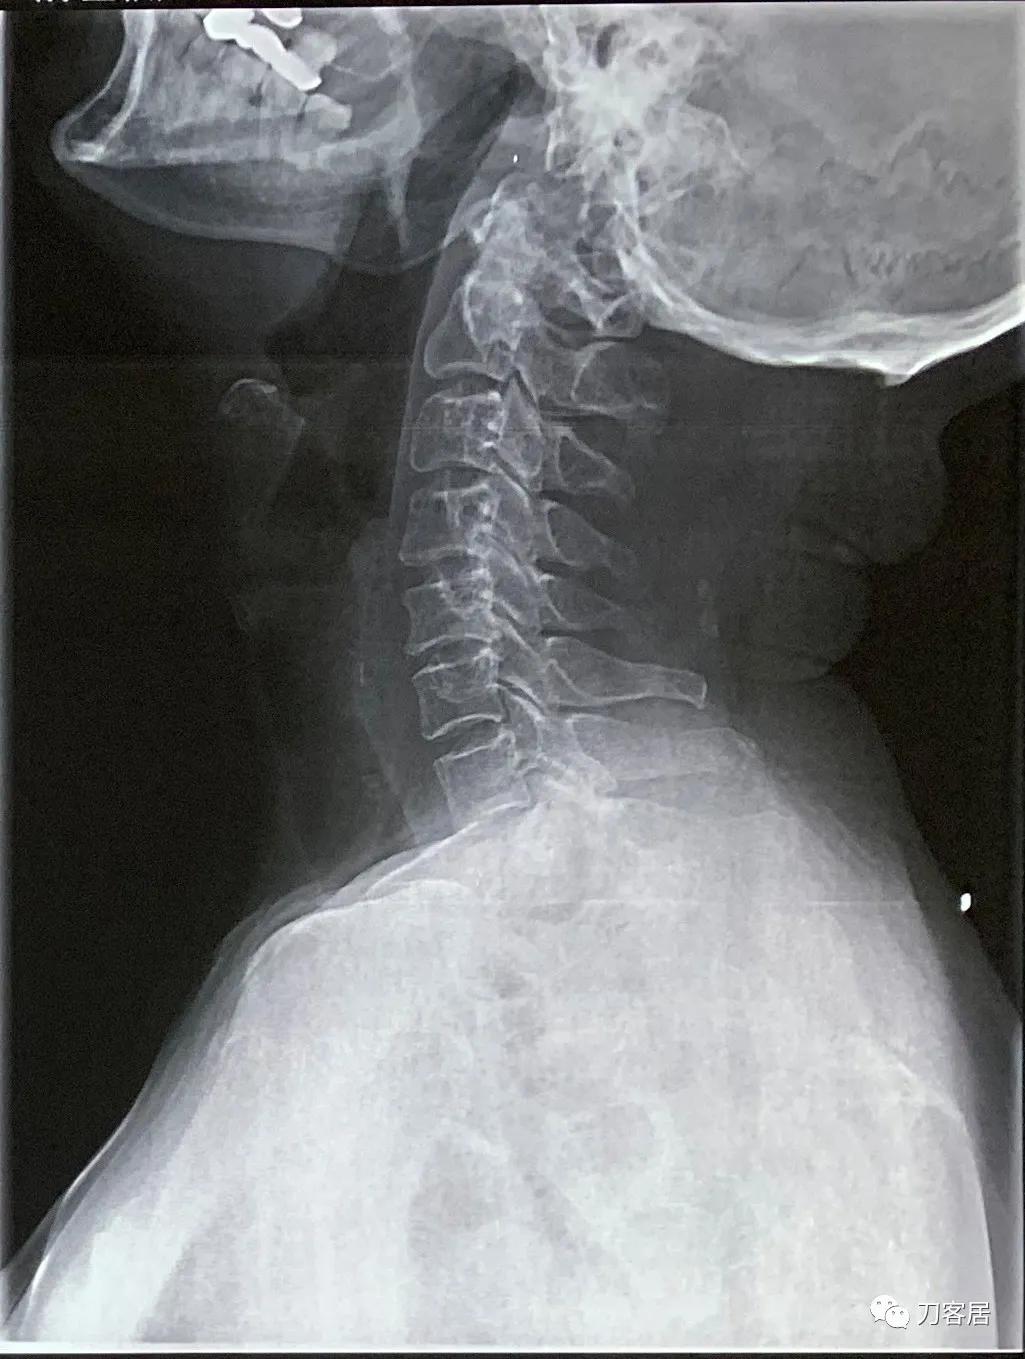

图8. 20210721颈椎侧位X线片,颈椎曲度尚好。